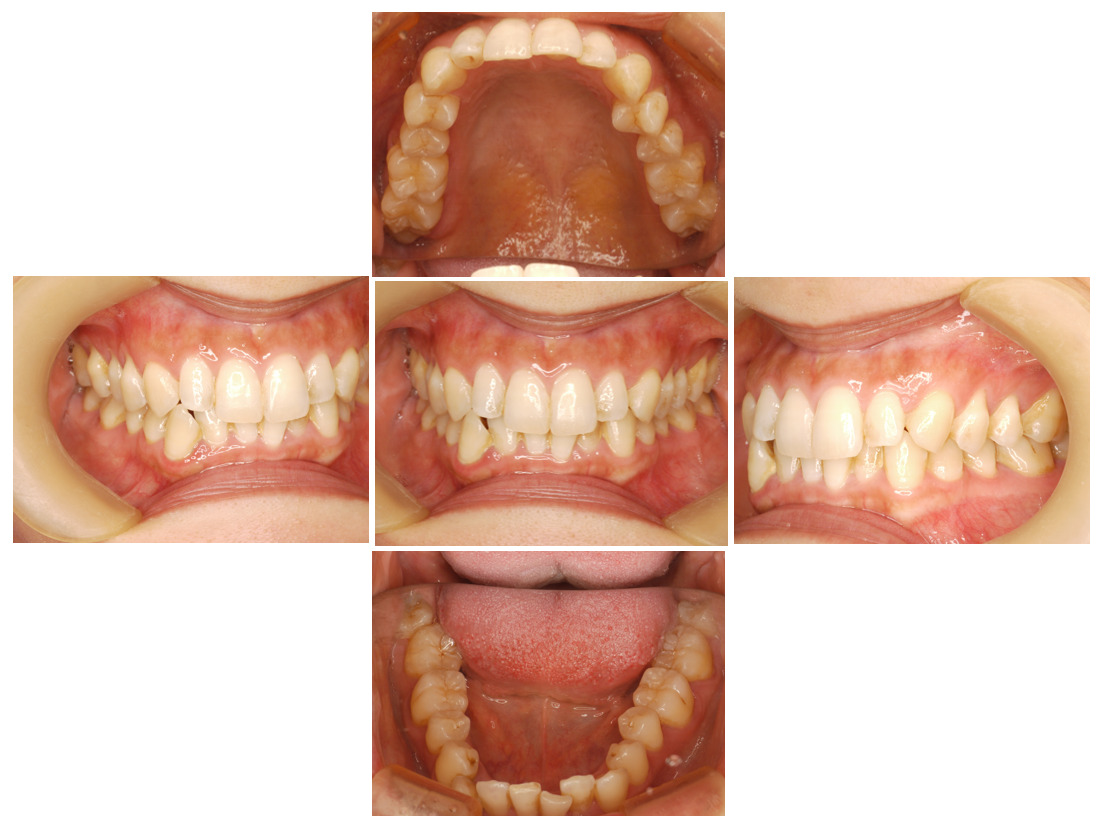

お口の中全体の写真

Before

| 治療に関する情報 | 下の前歯のガタツキ並びに全体の歯並びをインビザラインで矯正したケースです。 |

| 患者の症状 | 定期検診で通われていた患者で、下の前歯がガタツキが気になるということで矯正治療の相談をされた方です。 |

| 治療結果 | 下の歯列のガタツキは改善され、大きかった歯間の隙間も閉じました。 |